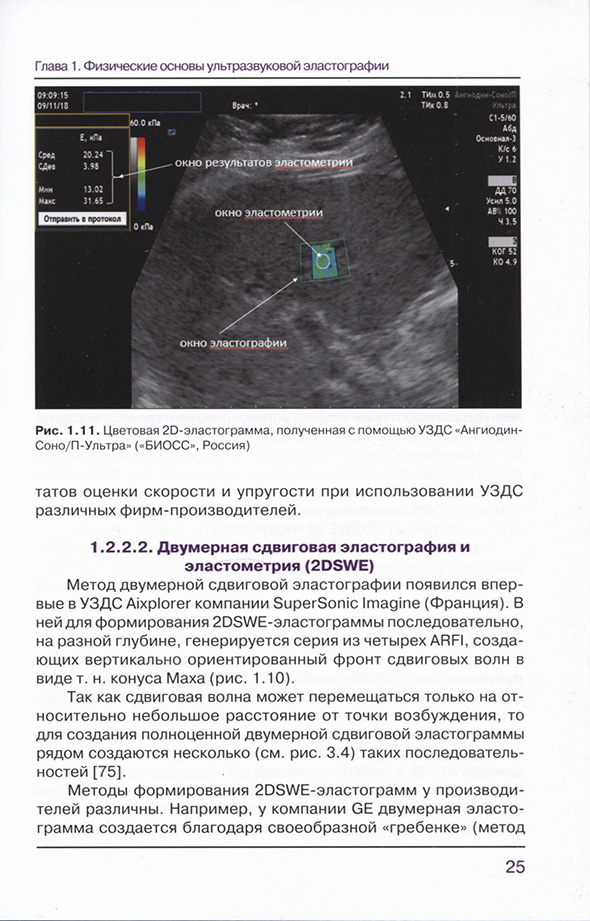

1.2.2.2. Двумерная сдвиговая эластография и эластометрия (2DSWE)